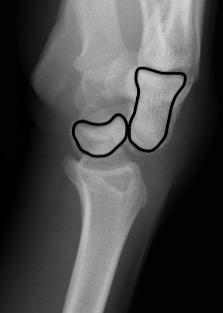

Lateral xray

Distal radius / lunate / capitate: not aligned, spilled teacup

Normal versus spilled tea cup appearance on lateral with spilled tea cup

1. Perilunate dislocation

Lunate remains aligned with distal radius

Capitate dislocates dorsally

2. Lunate dislocation

Lunate dislocates / usually volar

Carpus remain aligned with distal radius